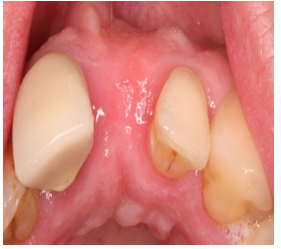

• Peri-apical lesion UR1 seen on radiograph

• RCT carried out 10 years ago

• Asymptomatic

• No clinical signs

• Is the UR1 restorable?

CBCT scan OF UR1 Site, peri-apical cyst?

Extraction of the UR1

Single Implant placement UL1 for cantilever bridge